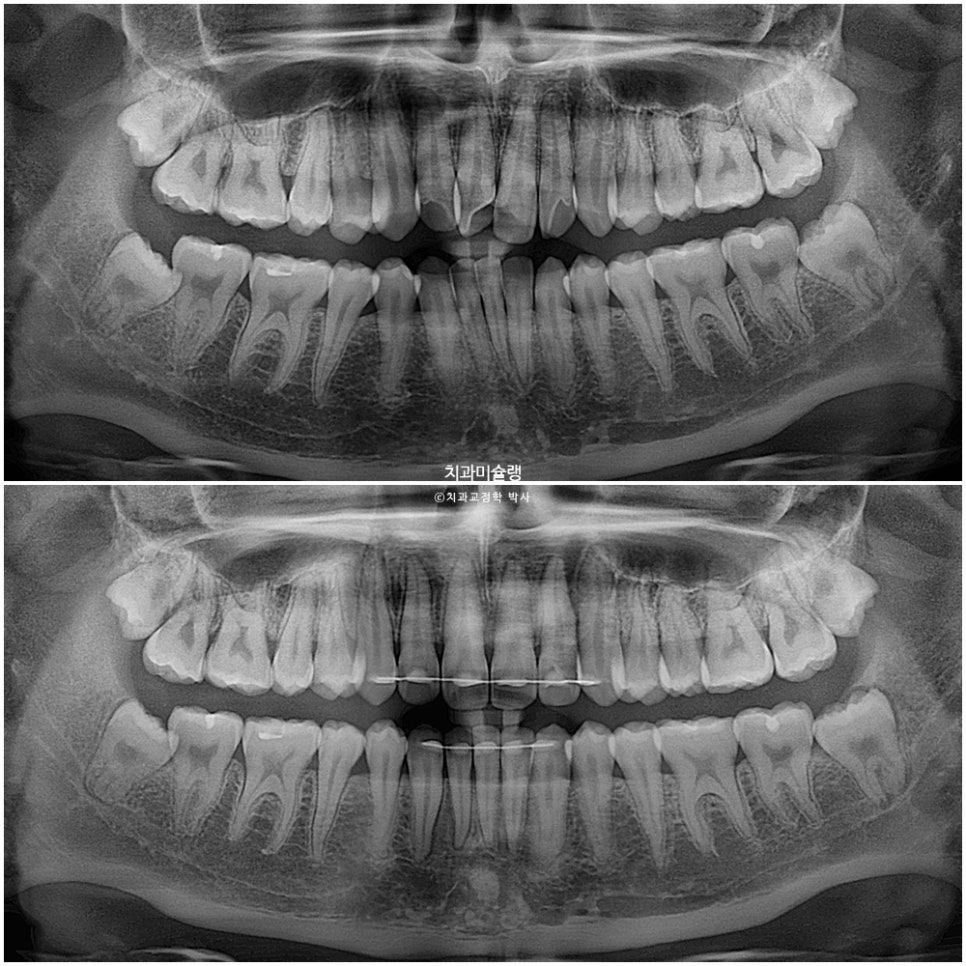

사랑니를 안빼고 교정을 했기 때문에 사랑니가 그대로 남아있습니다.

언젠가 사랑니에 문제가 생긴다면 그땐 발치를 해야겠죠.

교정기간동안 치근흡수는 없으며 기울어져 있던 앞니 뿌리는 평행하게 재정렬되었습니다.